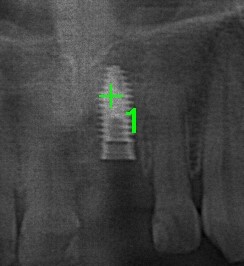

インプラントを埋入したレントゲンです。

仮歯が同日に入ったところです。